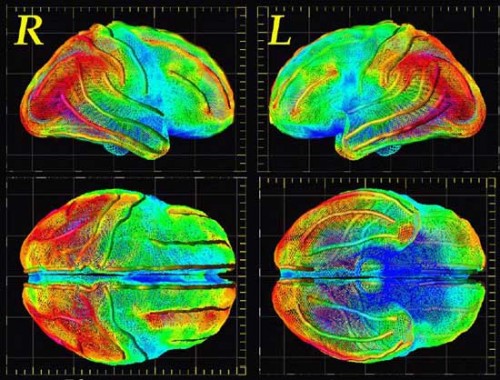

Con queste parole, riportate dalla rivista di divulgazione e revisione scientifica Journal of Psychiatry, Jason J. Wolff, ricercatore capo presso il Carolina Institute for Developmental Disabilities della North Carolina University, avrebbe commentato la possibilità, scoperta ed individuata dal team di neurologi al proprio servizio, di diagnosticare l’autismo, già a 6 mesi di vita, grazie alla corretta applicazione delle più moderne tecniche di neuroimaging.

In particolare, stando a quanto dichiarato dagli scienziati coinvolti nel progetto, il sistema nervoso centrale dei bambini autistici mostrerebbe, sin dai primissimi mesi di vita, significativi tratti caratteristici che, in definitiva, lo renderebbero estremamente differente da quello dei bambini sani.